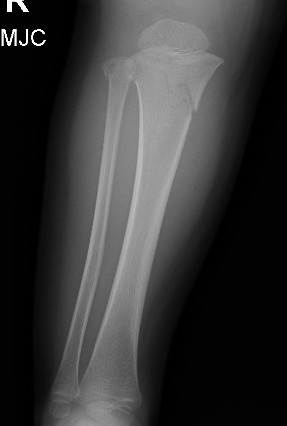

Proximal metaphyseal tibial fracture

Cozen phenomenon

Delayed valgus deformity secondary to medial tibial elongation

Natural history

Papamerkouriou et al J Child Orthop 2020

- 33 patients with Cozen fracture

- 73% developed medial elongation over a mean of a year

- cases then tended to resolved over time to initial post treatment angles